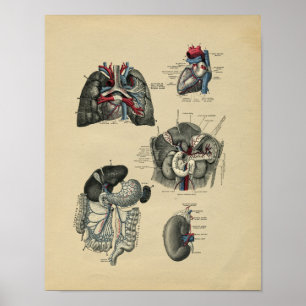

Impressão humano da anatomia dos órgãos interno

Preço15,60 €